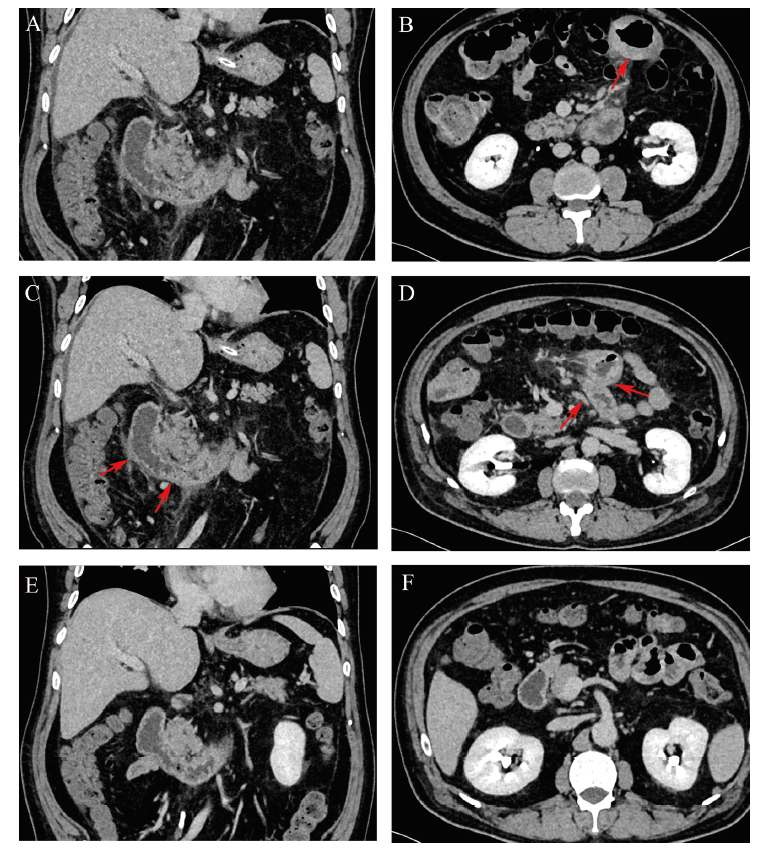

图1 以肠梗阻为首发表现的成人IgA血管炎患者CT图

注:A、B为入院前CT,CT显示脾门下方混杂密度团块影,结肠造影显示脾区可见斑片状高密度影(箭头所指为回肠肠壁增厚);C、D为患者入院第2日CT图,十二指肠降段、水平段及空肠肠壁增厚(箭头所指),伴有周围肠系膜脂肪间隙模糊;E、F为激素治疗后(入院第12日)CT图,十二指肠降段、水平段及空肠近段肠壁未见增厚。

患者男,50岁。因腹胀、腹痛7 d于2020年6月19日入院。患者7 d前饮酒后出现腹胀、腹痛,为全腹胀痛,伴有停止排气、排便,伴恶心、呕吐,呕吐物为胃内容物(不含血液),无发热。患者就诊于当地社区医院未明确诊断,给予对症治疗后症状无缓解。6 d前就诊于河北省人民医院急诊科,实验室检查示白细胞16.66×109/L,中性粒细胞84.0%,嗜酸性粒细胞0.5%,血红蛋白131 g/L;血小板238×109/L;CRP 59.37 mg/L。腹部和盆腔CT平扫+增强示部分小肠肠壁增厚伴强化,考虑炎性病变可能性大;升结肠肠腔扩张,肠内容物增多(图1A、B)。考虑“不完全性肠梗阻”,给予“甘油灌肠剂清洁灌肠、乳果糖通便和双歧杆菌调节肠道菌群”等治疗后,排黑色稀便3次,腹胀较前稍减轻,但仍有腹痛,排气、排便减少,进食较少。随后就诊于消化科门诊,实验室检查示白细胞25.54×109/L,中性粒细胞87.80%,嗜酸性粒细胞0,血红蛋白158 g/L,血小板386×109/L,CRP 126.37 mg/L,总胆红素20.1 μmol/L。患者以“肠梗阻”收住院。既往有高血压病史10余年,口服苯磺酸氨氯地平5 mg/d降压治疗,血压控制在120~130 / 80~85 mmHg(1 mmHg = 0.133 kPa)。否认食物及药物过敏史。

初步诊断:不完全性肠梗阻、高血压病2级(高危),给予胃肠减压、补液、抗感染、清洁灌肠通便等治疗2 d,患者腹胀、腹痛无明显好转,入院第2日复查腹部平扫+增强CT提示十二指肠降段、水平段及空肠近段肠壁增厚,周围肠系膜脂肪间隙模糊并多发肿大淋巴结,考虑炎性病变可能性大(图1C、D),腹腔少量积液。入院第5日胃镜检查示十二指肠多发糜烂、小溃疡,图2A~C);在十二指肠降部取活检4块送病理示黏膜中度慢性炎症,间质水肿,少量嗜酸性粒细胞浸润伴炎性坏死。当日晚上患者开始出现双下肢皮疹,位于双足背部、踝部、双下肢伸侧对称性分布,米粒大小紫红色皮疹,高出皮面,压之不褪色(图3A),并伴有双膝关节明显肿痛,行走困难。

该病例特点:①患者中年男性,急性病程。②主因腹痛、腹胀7 d入院,为不完全性肠梗阻的表现,入院后第5日出现双下肢紫癜样皮疹、关节肿痛。③查体腹部膨隆,肠鸣音减弱。④立位腹平片提示左中上腹小气液平;腹部CT提示整个小肠炎性改变。⑤常规通便、灌肠、胃肠减压效果欠佳。反复询问患者病史,患者发病前无感冒、无药物服用史、否认食物过敏史等情况。因此,修正诊断:①IgA血管炎,混合型(病因不明);②高血压病2级(高危)。给予甲泼尼龙琥珀酸钠80 mg/d静脉滴注,用药2 d,患者腹痛、腹胀、双膝关节肿痛明显减轻,治疗5 d复查腹部CT提示整个小肠炎性改变消失。同时复查肝功能示ALT 213 U/L,AST 157.7 U/L,γ-谷氨酰转移酶242.8 U/L,碱性磷酸酶127.8 U/L,予以保肝治疗。激素治疗11 d后,患者腹痛、腹胀症状缓解,双下肢足背皮肤紫癜消退(图3B),查体未见阳性体征。入院第12日查双侧膝关节彩超未见异常;并复查腹部CT提示整个小肠炎性改变消退(图1E、F)。激素治疗11 d后复查血常规示白细胞13.04×109/L,中性粒细胞73.4%,嗜酸性粒细胞百分比0.2%,血红蛋白108 g/L,血小板252×109/L;CRP 4.7 mg/L。肝功能示ALT 81.6 U/L,AST 30 U/L,白蛋白33.0 g/L,γ-谷氨酰转移酶234 U/L,碱性磷酸酶128 U/L,总胆红素7.2 μmol/L。复查胃镜提示十二指肠球部及降部黏膜炎症明显减轻(图2D~F);同时完善结肠镜检查提示直肠炎,直肠取病理活组织检查提示直肠慢性炎症。